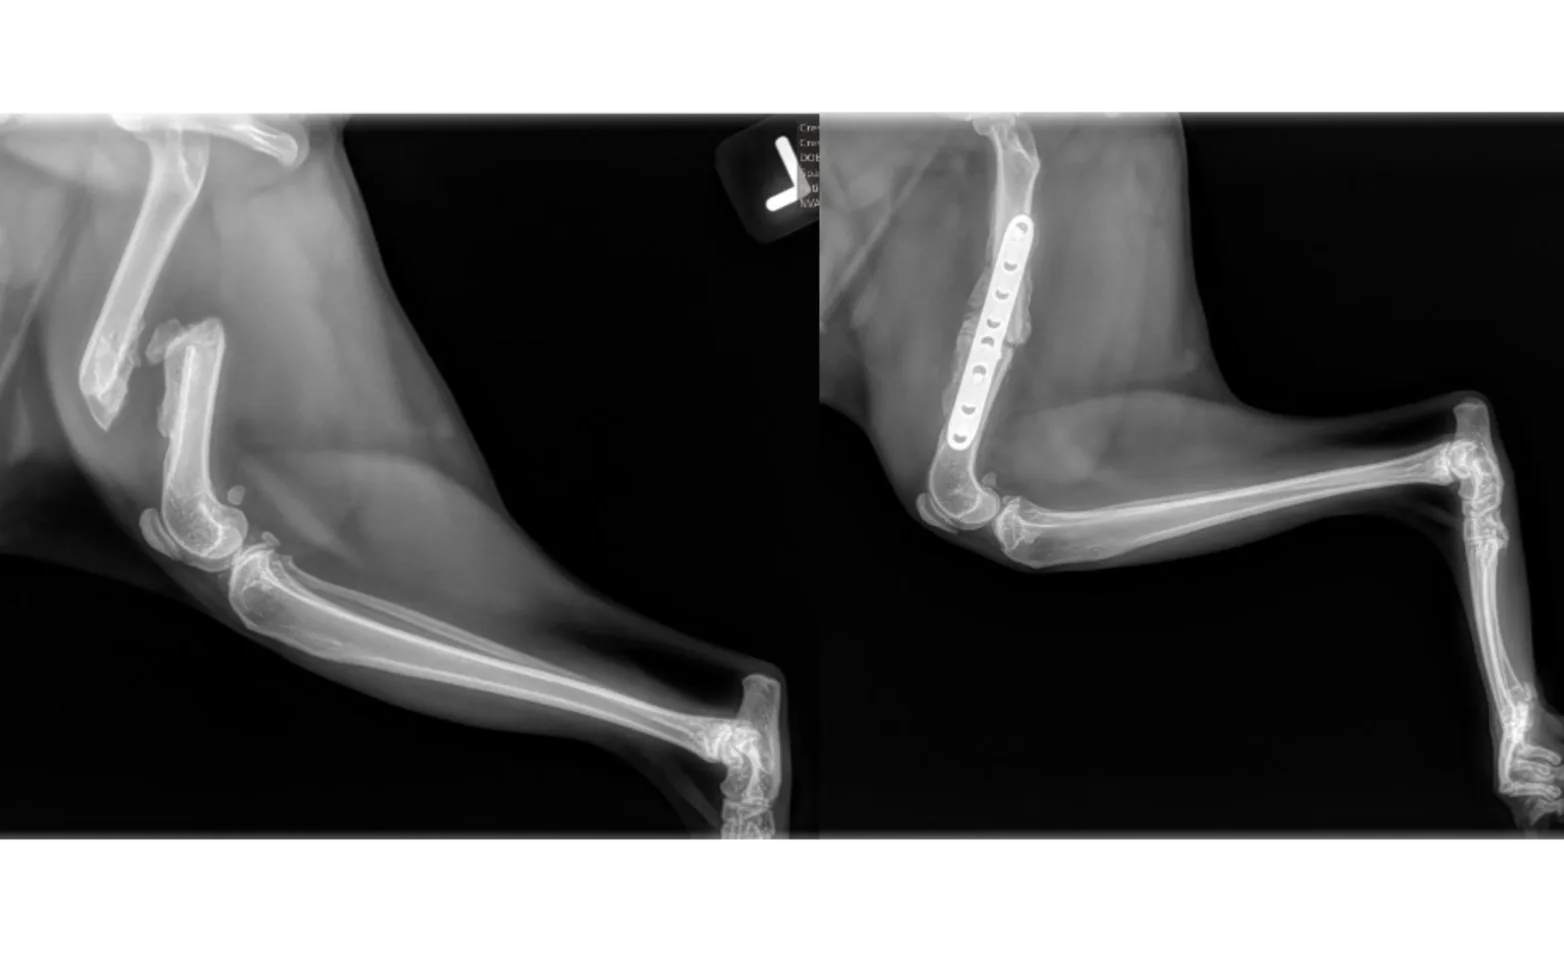

In the images above we see before and after pictures of a kitty's femur. He went missing for a month and came home with and fractured femur! The femur had actually begun the healing process; however, the bone was not healing in the proper location (the ends are very overlapped as you see here), and the kitty could not walk normally or without pain. A large amount of soft and hard callous wrapped around the bone and had to be broken down to re-align the fragments to allow placement of the plate. Within just a few days, this patient was walking again. The sent set of radiographs occurred about 4 weeks later and we can see new bone formation at the fracture site. This kitty still has a few more weeks before we can give the “all clear,” but given how well things have gone, we think he will do very well and heal with no complications.